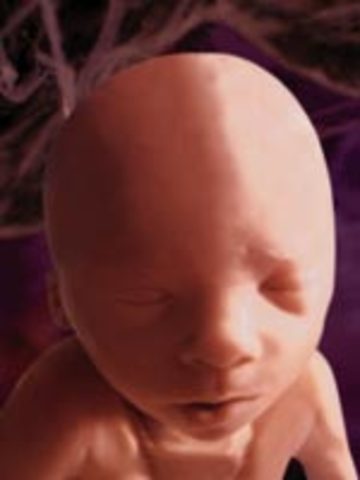

• week 30

week 30

Baby controls its own body temperature. Skin is becoming smoother.

• week 31

week 31

Eyes react to light and darkness. A loud noise may cause baby to jump.